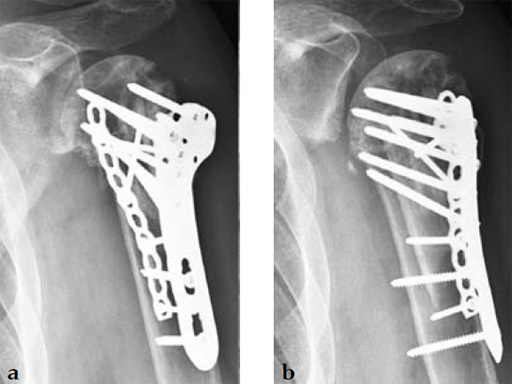

A 72-year-old woman suffered a four-part fracture of the left proximal humerus following a fall from a standing height. The patient underwent open reduction and internal fixation of the proximal humeral fracture.

Case provided by Dean G Lorich, New York, New York, USA